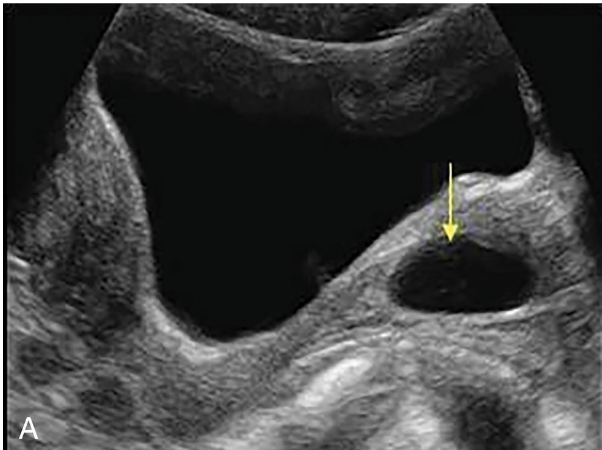

• Benign cysts in the cervix which result from chronic cervicitis and are seen frequently in middle-aged women. This cyst results from an obstructed dilated transcervical gland and is also called an epithelial inclusion cyst.

• Chronic inflammatory retention cysts

• Asymptomatic although may cause pain/bleeding with coitus

• On sonographic evaluation include:

• discrete

• round

• fluid-filled

• anechoic

• usually measuring less than 2 cm;

• they may be multiple.

• Occasionally, nabothian cysts may have internal echoes that may be caused by hemorrhage or infection.

Nabothian Cyst